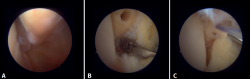

Anterior arthroscopic view

Twenty percent of the ATFL is intra-articular(7). On adopting an anteromedial access of the ankle, directing the arthroscope laterally, we can see the distal fibers of the ATFL with their oblique distribution and their continuation with the anterior talofibular ligament (Figure 2). If we move into the tibiotalar joint, we see the distal tibiofibular joint with the syndesmotic recess occupied by synovial tissue (Figure 3).

Posterior arthroscopic view

From the posterolateral approach we identify the lateral (fibular) malleolus and, from here, we visualize the intra-articular fibers of the PTFL, which run obliquely and insert into the distal portion of the tibia. We also see the distal thickening of the PTFL (transverse ligament) in continuity with the posterior lip of the distal tibia (Figure 4).

Figure 2. Anterolateral arthroscopic view of the right ankle. 1: talar dome; 2: anterior aspect of the tibia; 3: fibula; 4: distal fibers of the anterior tibiofibular ligament; 5: anterior talofibular ligament.

Figure 3. Anterolateral arthroscopic view of a right ankle on entering the tibiotalar zone. 1: talar dome; 2: articular aspect of the tibia; 3: fibula; 4: distal tibiofibular joint; 5: distal fibers of the anterior tibiofibular ligament.

Figure 4. Posterior arthroscopic view of a right ankle in which a symptomatic Stieda process has been resected. 1: posterior tibiofibular ligament; 2: transverse ligament; 3: talar dome; 4: distal tibia; 5: posterior subtalar joint; 6: flexor hallucis longus.